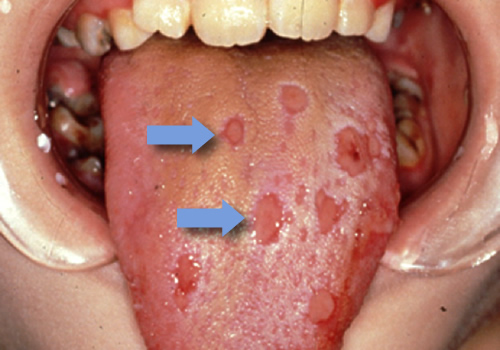

ヘルペスウイルスによる口内炎

疱疹性歯肉口内炎;ヘルペス性口内炎とも呼ばれ、単純ヘルペスウイルスによって発症し、接触感染や飛沫で感染します。

少し形態が違いますが、帯状疱疹ウイルスによる感染は、疼痛や水疱を口腔粘膜、皮膚に生じ、それが破れてびらんや潰瘍に変化していきます。またEBウイルス、HIVウイルス感染症などでも口内炎が出現します。